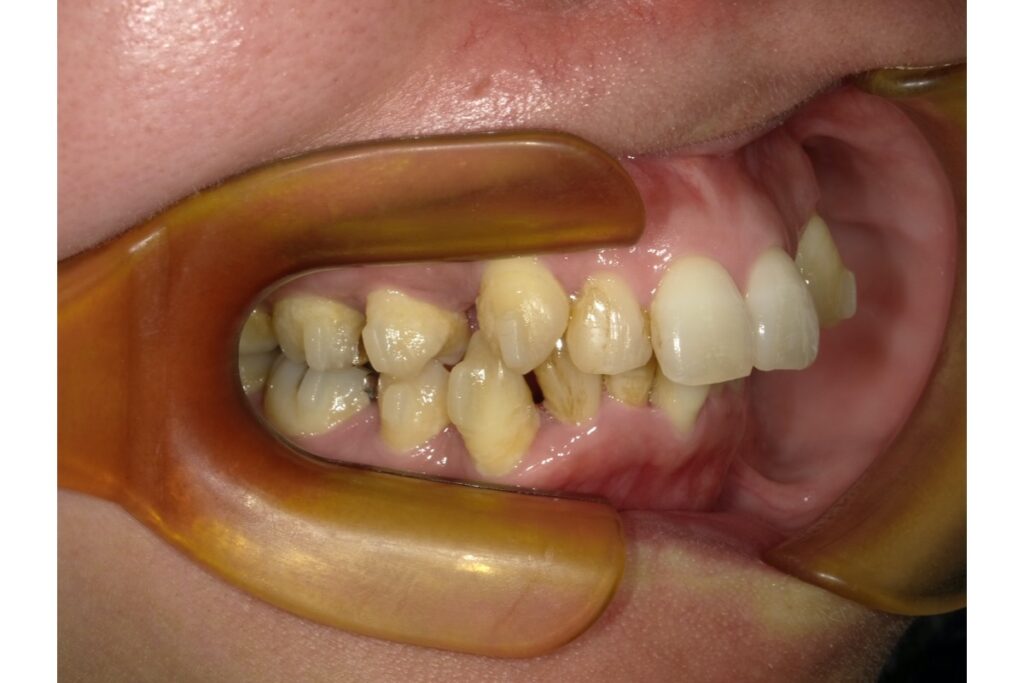

・叢生(歯のガタガタ)

圧力の影響で歯の生えるスペースが狭くなり、結果的に歯が重なり合って「ガタガタ」になる叢生(そうせい)も、頬杖が関与しているケースがあります。